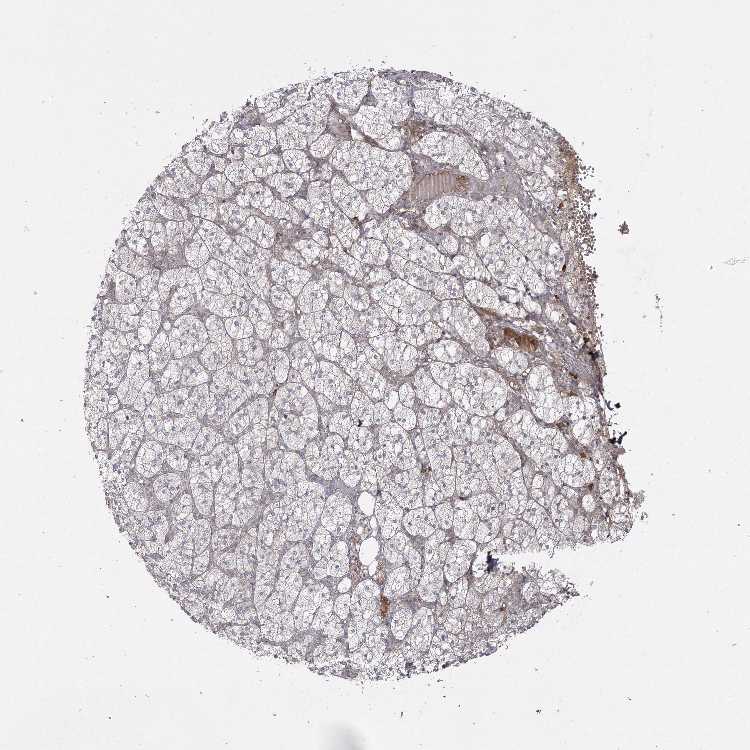

ADRENAL GLAND - Antibody stainingi

Antibody staining in the annotated cell types in the current human tissue is reported as not detected, low, medium, or high, based on conventional immunohistochemistry profiling in selected tissues. This score is based on the combination of the staining intensity and fraction of stained cells.

Each image is clickable and will lead to virtual microscopy that enables deeper exploration of all samples and also displays staining intensity scores, fraction scores and subcellular localization as well as patient and tissue information for each sample.

Antibody HPA035923Antibody HPA035924

Glandular cells HighLow